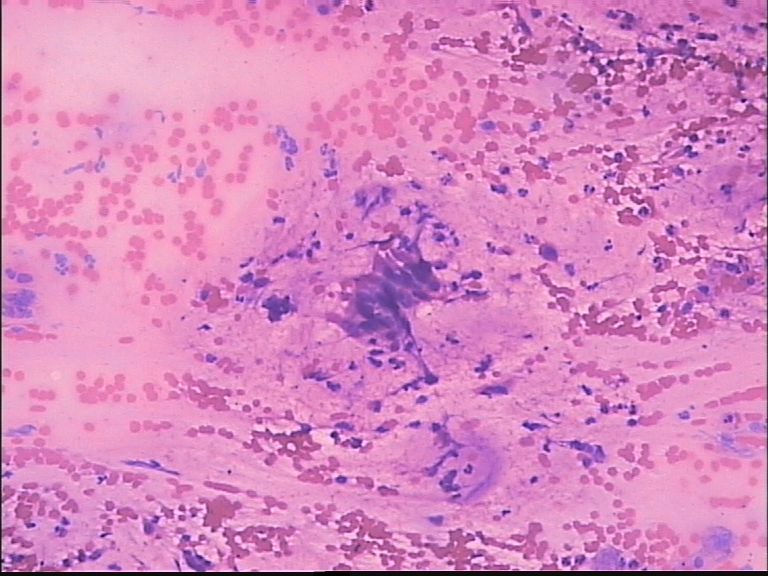

男 70岁,ct肺部见一肿块:结核?肺癌?

支气管镜活检看到的是粘膜慢性炎伴多核巨细胞反应。